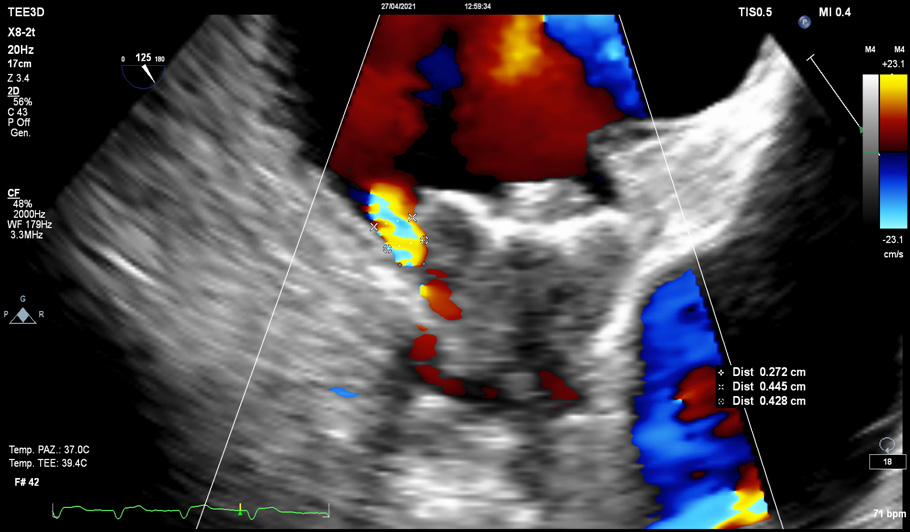

Either TOE or CCTA is highly recommended at 45 days (

Reassess the device position and stability; device embolism may be asymptomatic (Fig. 8).

• Assess for any residual or new PDL; PDL

Fig. 9.Para-device leak (PDL). PDLs